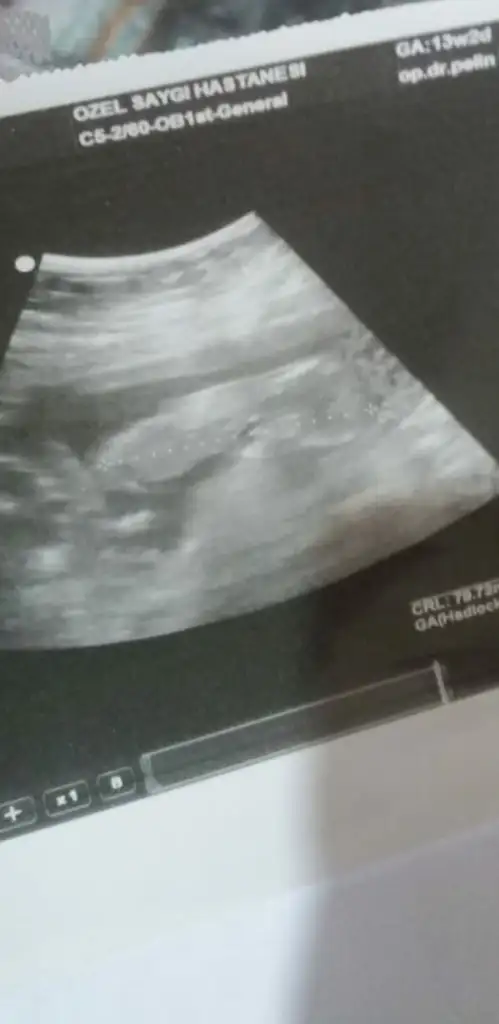

Ikra meyra Ikra meyra 13+1 haftalık karından ultrason görüntülerini yorumlayabilir misin?☺️🙏

• E3F032FD-DEC1-441B-9C2F-74E6BCB4031B.webp

E3F032FD-DEC1-441B-9C2F-74E6BCB4031B.webp

13,5 KB · Görüntüleme: 99